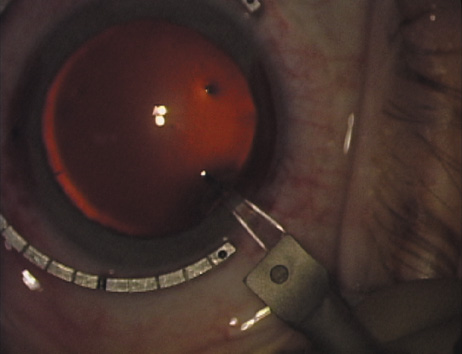

with the fixation ring/gauge (Fig. 4). Alternatively, various press-on markers are available, such as

those made by Rhein Medical (Dell-Nichamin Marker, Nichamin-Kershner

Marker, or the Ruminson Marker) (Fig. 5). ASICO and other instrument companies offer a full line of dedicated

markers, rings, and blades for performing LRIs.  Fig. 4. The Nichamin Fixation Ring and Gauge serves to both fixate the globe and

delineate the extent of arc to be incised; a two-cut radial marker may

be used to mark the extent of arc to be incised, and the Mastel Nichamin

Force AK Diamond Blade with preset depth of 600 microns. Fig. 4. The Nichamin Fixation Ring and Gauge serves to both fixate the globe and

delineate the extent of arc to be incised; a two-cut radial marker may

be used to mark the extent of arc to be incised, and the Mastel Nichamin

Force AK Diamond Blade with preset depth of 600 microns.